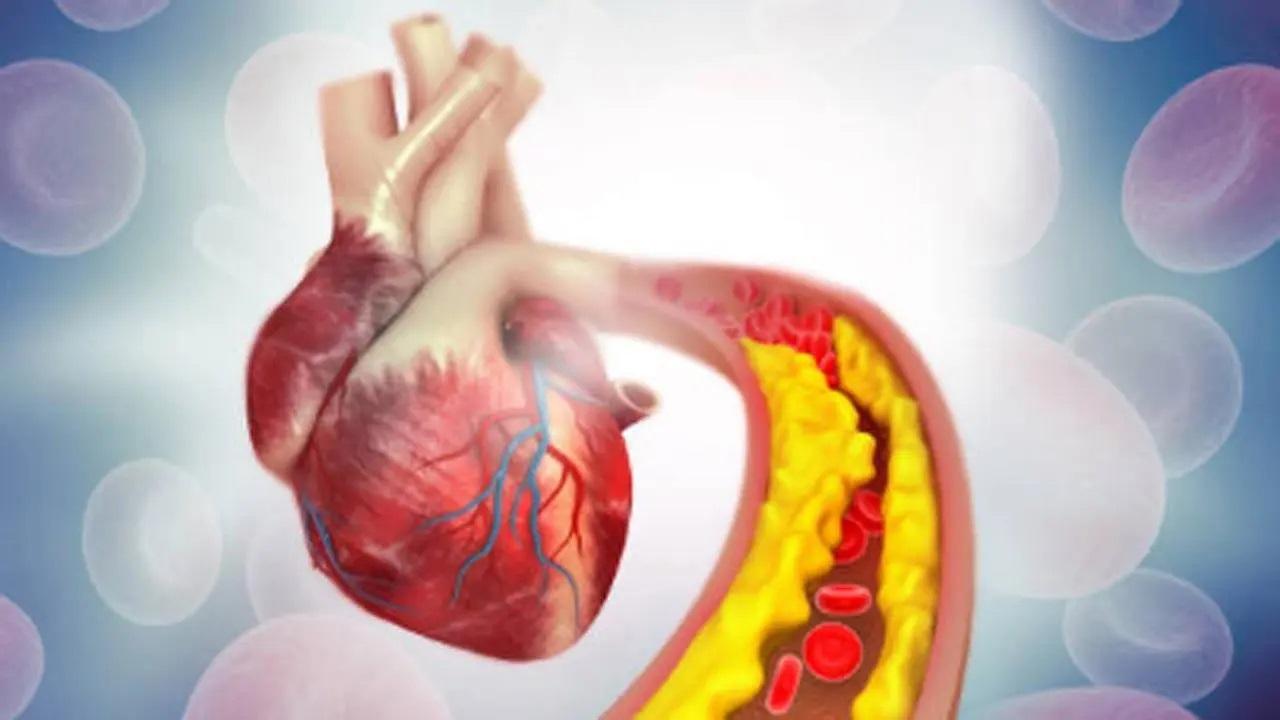

O estudo testou o CTX310, uma terapia única de edição genética CRISPR-Cas9 que usa partículas à base de gordura para transportar ferramentas de edição CRISPR para o fígado, desligando o gene ANGPTL3. Desligar esse gene reduz o colesterol LDL (ruim) e os triglicerídeos, duas gorduras do sangue ligadas a doenças cardíacas, de acordo com um comunicado divulgado segunda-feira pela Universidade Monash da Austrália.

Na dose mais elevada, um tratamento único com CTX310 resultou numa redução média do colesterol LDL em 50 por cento e dos triglicéridos em 55 por cento, permanecendo baixo durante pelo menos 60 dias após duas semanas de tratamento, disse, acrescentando que o colesterol LDL e os triglicéridos foram reduzidos em quase 60 por cento entre todos os participantes com várias doses, com apenas efeitos secundários ligeiros e de curto prazo relatados.

É importante ressaltar que o CTX310 é a primeira terapia a alcançar grandes reduções no colesterol LDL e nos triglicerídeos ao mesmo tempo, marcando um avanço potencial para pessoas com distúrbios lipídicos mistos que apresentam elevações em ambos, de acordo com o ensaio publicado no New England Journal of Medicine.